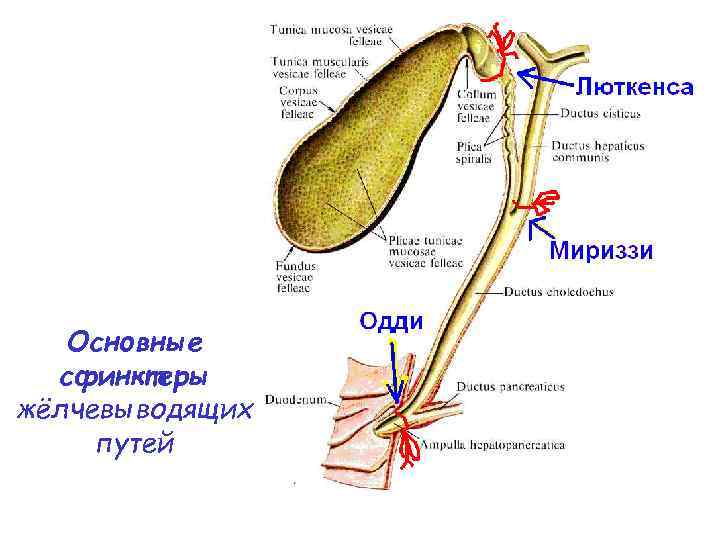

Желчевыделение Выделяют 3 сфинктера: • шейки желчного пузыря (Люткенса) • в месте слияния пузырного и общего печеночного протока (Мириззи) • в концевом отделе общего желчного протока (Одди)

Желчевыделение Выделяют 3 сфинктера: • шейки желчного пузыря (Люткенса) • в месте слияния пузырного и общего печеночного протока (Мириззи) • в концевом отделе общего желчного протока (Одди)

Основные сфинктеры жёлчевыводящих путей

Основные сфинктеры жёлчевыводящих путей